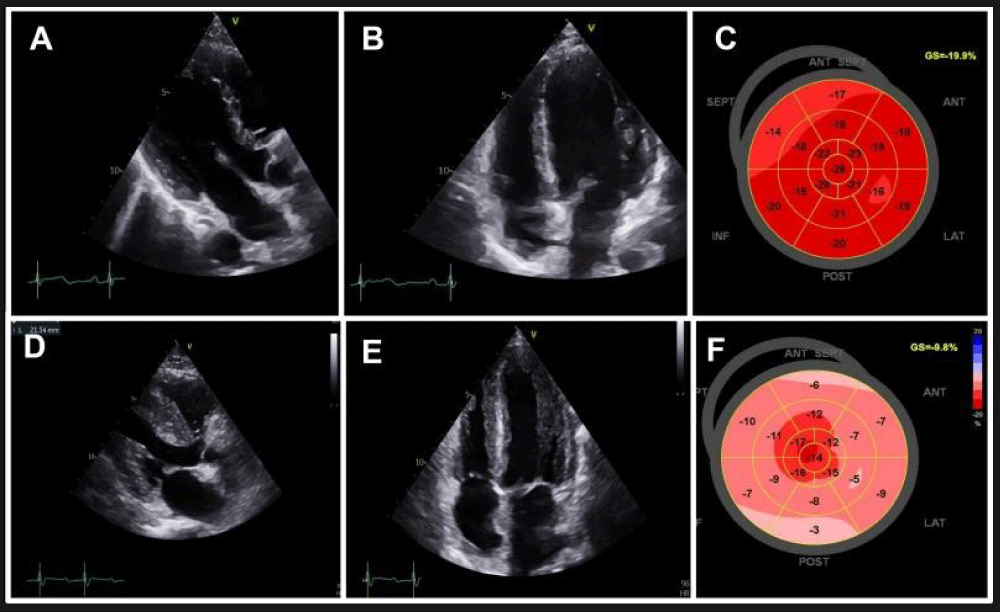

Figure 2: CMR and histologic findings in March 2023 (A, B, C, D) and in May 2023 (E, F, G, H, I).

A: Four-chamber view on cine-steady state free precession CMR sequence showing normal left ventricular wall thickness.

B: Late gadolinium enhancement sequence showing no abnormalities.

C: T1 mapping sequence indicating an absence of T1 elevation.

D: T2 mapping sequence indicating an absence of T2 elevation.

E: Four-chamber view on cine-steady state free precession CMR sequence showing increased left ventricular wall thickness. Pleural effusion can be seen (black star).

F: Late gadolinium enhancement sequence showing late enhancement in the lateral and antero-septal wall (white arrows).

G: T1 mapping sequence revealing an increase in T1.

H: T2 mapping sequence revealing an increase in T2.

I: Upon staining with hematoxylin-eosin, histological images of the endomyocardial biopsy reveal myocardial tissue containing inflammatory cells (neutrophils and mononuclear cells) and areas of myocyte damage.

The coronary computed tomography scan did not reveal any abnormalities. The cardiac magnetic resonance imaging (CMR) showed borderline T2 values around 57 ms on the septum, but there were no abnormalities in T1 and extracellular volume. There was no late gadolinium enhancement. The diagnosis of myocarditis was not retained according to the modified Lake Louise criteria (Figure 2 A-D). Control troponin level remained at 2 times normal, and the patient was still asymptomatic. A CMR check-up at 3 months was initially scheduled. Pembrolizumab was resumed after all explorations.

In late May 2023, the patient was admitted to the cardiac intensive care unit due to quickly worsening dyspnea. Her NT-pro-BNP level had significantly increased to 4300 pg/mL, and her troponin level was three times the normal limit. She exhibited severe hyperlactatemia at 6 mmol/L. This hyperlactatemia remained stable, plateauing around 5-6 mmol/L, despite the initial absence of other signs of peripheral hypoperfusion for several days. On EKG, first-degree atrioventricular block and incomplete right bundle branch block were observed. TTE revealed left ventricular hypertrophy with a hyper-echogenic myocardium. While the left ventricular ejection fraction was normal (62%), the global longitudinal strain was altered with apical sparing (GLS = -9.8%). The right ventricle wall was also thickened and there was a pericardial effusion (Figure 1 D-F). CMR was performed and revealed features of acute myocarditis with diffuse myocardial edema and the presence of late gadolinium enhancement predominantly in the lateral wall, forming a very nodular shape (Figure 2 E-H). There was also a widespread and significant increase in extracellular volume between 45% and 50%. A pericardial effusion and right ventricle hypertrophy were also present. Left ventricular ejection fraction was preserved (69%). An abdominopelvic computed tomography scan performed due to hyperlactatemia revealed a heterogeneously enlarged liver and spleen with multiple secondary lesions, extensive intraperitoneal effusion, and mesenteric infiltration which could explain the hyperlactatemia.

An endomyocardial biopsy confirmed ICI-associated acute myocarditis. On hematoxylin-eosin stain, histologic images from endomyocardial biopsy show myocardial tissue with inflammatory cells (neutrophils and mononuclear cells) and foci of myocyte damage (Figure 2 I).